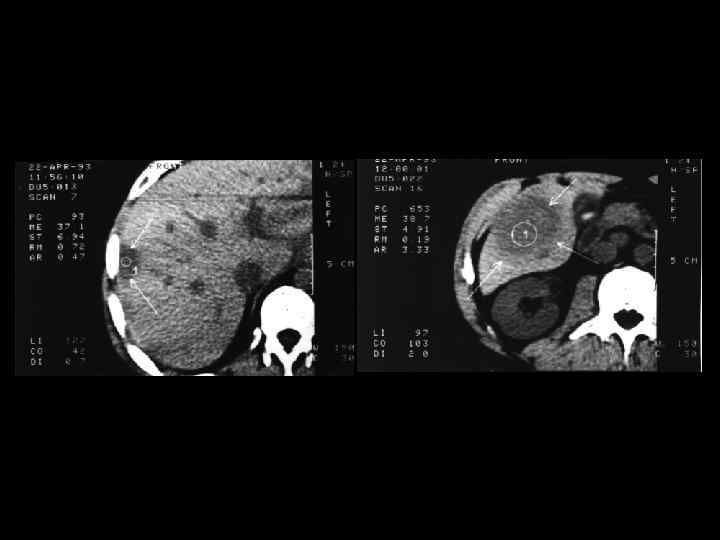

АКТУАЛЬНЫЕ ВОПРОСЫ РЕНТГЕНОЛОГИИ ЛУЧЕВАЯ ДИАГНОСТИКА ОЧАГОВЫХ ПОРАЖЕНИЙ ПЕЧЕНИ КАВЕРНОЗНАЯ ГЕМАНГИОМА Компьютерно-томографическая семиотика: - ограниченный участок пониженой плотности (до 50 -30 ед Н) - границы могут быть ровными, но нечеткими - после введения РКВ - характерный феномен усиления плотности от периферии к центру в течении нескольких минут после внутривенного введения РКВ

Клиническое наблюдение. Пациентка С. , 1953 г. р.

Та же пациентка